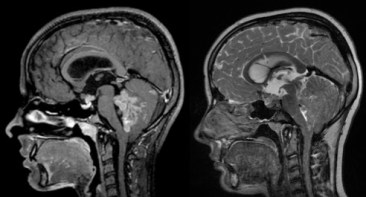

elle peut être très évocatrice, montrant une tumeur spontanément hyperdense en scanner, avec une prise de contraste hétérogène et une hypercellularité bien montrée par la séquence en diffusion.

l’aspect radiologique peut cependant être trompeur.

on recherche systématiquement des métastase par l‘IRM cranio-spinale.

le plus souvent, on réalise en urgence une ventriculocisternostomie endoscopique ; ceci permet de mettre le patient à l’abri du risque d’engagement et de lésion des nerfs optiques, mais ne résout pas le problème de la compression du tronc cérébral.